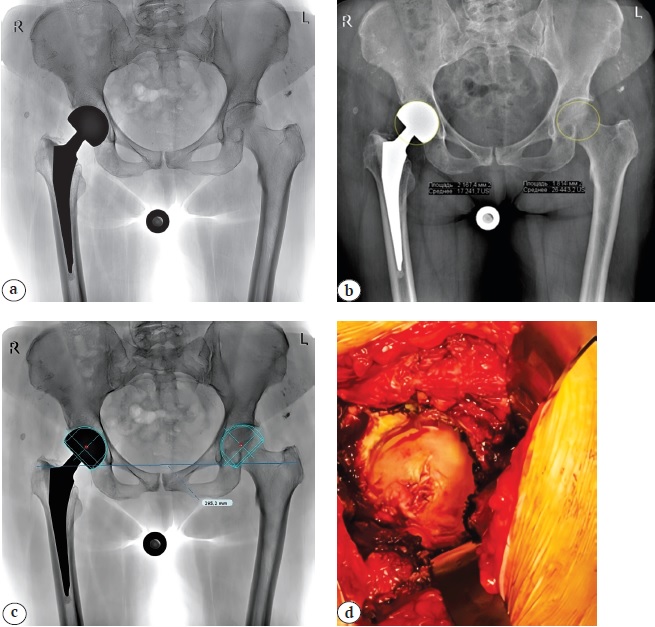

Рис. 3. Клинико-рентгенологическая картина эрозии хрящевой ткани вертлужной впадины, развившейся у пациентки 77 лет через 2,5 года после первичной гемиартропластики по поводу перелома шейки правой бедренной кости:

а — первичный обзорный рентгеновский снимок таза (через 2,5 года после эндопротезирования) — определяется биполярный гемиэндопротез;

b — расчет площади окружности головки бедренной кости с левой здоровой стороны (18,1 см2), справа — расчет площади окружности биполярной головки эндопротеза — 21,6 см2, увеличение данного параметра на 3,5 см2;

c — данные предоперационного планирования, выполненного в программе TraumaCad 2.5.7. Размер головки гемиэндопротеза (50 мм) правого ТБС спроецирован на левую сторону. Отмечается захождение шаблона на контуры вертлужной впадины;

d — эрозия вертлужной впадины, хрящевая ткань отмечается только по периферии окружности в области крыши

Figure 3. Clinical and radiographic picture of acetabular cartilage erosion in a 77-year-old patient, developed 2.5 years after primary hemiarthroplasty for the fracture of the right femoral neck:

a — initial plain pelvic X-ray (2.5 years postop) showing a bipolar prosthesis;

b — calculation of the femoral head circumference area: 18.1 cm2 on the healthy left side, 21.6 cm2 on the right side with the bipolar prosthesis, indicating an increase of 3.5 cm2;

c — preoperative planning using TraumaCad 2.5.7 software: hemiarthroplasty prosthesis head size (50 mm) from the right hip joint projected onto the left side reveals the overlap of the template with the acetabular contours;

d — acetabular erosion: cartilage tissue is present only along the peripheral circumference in the acetabular roof area